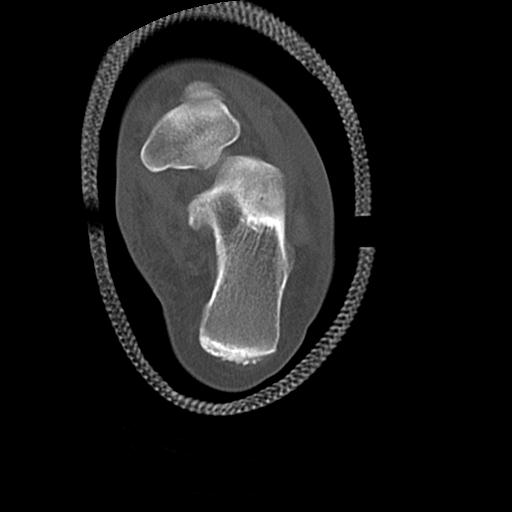

49554 3/13 膝 4R 3/16 4R 1/18 2R 78歳男性 膝蓋骨骨折